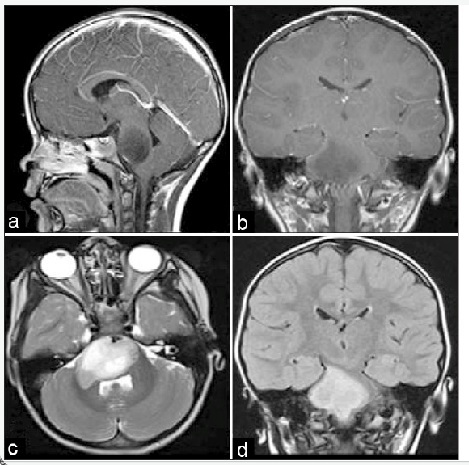

Seorang anak berusia lima tahun dengan tangan dominan sebelah kanan dinyatakan telah memiliki epilepsi sejak 4 tahun dan sering mengalami kejang motorik fokal yang persisten. Hasil pemeriksaan menunjukkan adanya gangguan perkembangan, perburukan IQ verbal dan hemiparesis sebelah kanan. EEG dan SPECT menunjukkan beberapa fokus epileptogenik pada lobus parietal kiri. Hasil MRI terlampir. Selain monitoring secara invasif, manakah dibawah ini pilihan terapi pembedahan yang paling mungkin :

B. Functional hemispherectomy

Rasmussen’s encephalitis is a rare syndrome manifested by intractable epilepsy, hemiplegia, and cognitive decline; left untreated it frequently also leads to loss of language development in young children. Epilepsia partialis continua is also a frequent feature. Imaging demonstrates diffuse hemispheric atrophy; histology demonstrates perivascular T-cell lymphocytic infiltrates. Given the inexorable decline if seizure control is not obtained, functional disconnection is indicated to also preserve language function and cognitive development. Hemispheric disconnection surgery is associated with a 70-80% success of seizure freedom in most series.